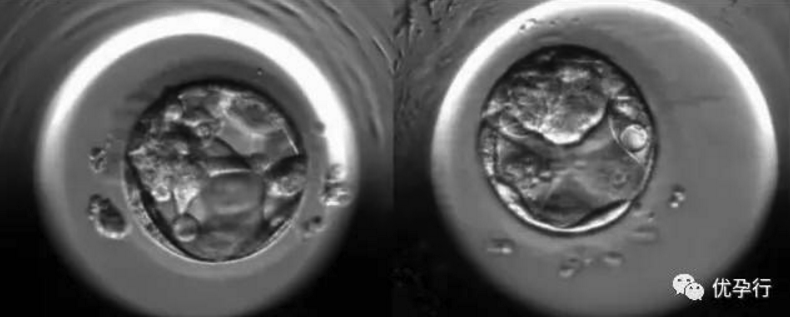

到了第5天,即成为具有一百多个细胞的囊胚。

在桑葚胚形成囊胚的这个阶段,对胚胎学家和实验室环境要求都非常高,培养皿内的温度、湿度、二氧化碳、氧气浓度等等都要尽量达到与子宫环境相同。

国内医院在受精卵发育成桑葚胚之前的阶段就停止培育了,因为实验室的环境与条件无法满足胚胎下一步的生长需求,如果继续培养,导致的结果是胚胎活力降低甚至死亡,这就是国内医院采取第3天的胚胎进行移植的原因。而美国因为有全球先进的实验室和全球经验丰富的生殖专家,所以采用的是第5天或第6天的囊胚进行移植。只有发育潜力好的胚胎才能形成囊胚哦,所以囊胚的着床率很高,且能提供更多的细胞进行基因筛查。